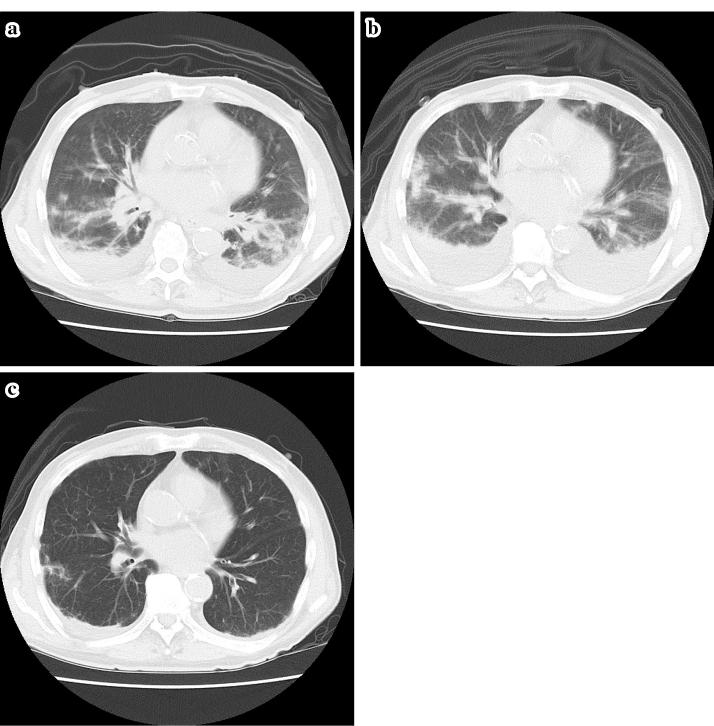

肺部嗜酸性粒细胞疾病中的肿瘤溶解样综合征:一例报告及文献复习

Tumor lysis syndrome (TLS) is a metabolic disorder that is generally associated with a malignancy leading to hyperuricemia, hyperphosphatemia, and acute kidney injury. On the other hand, we sometimes encounter these phenomena in nonmalignant disease, which has been referred to as tumor lysis-like syndrome in some studies. We herein experienced a case in which tumor lysis-like syndrome occurred in the course of therapy for eosinophilic disease of the lung, a nonmalignant disease. Even in nonmalignant disease, massive cell lysis induced by therapy can cause phenomena such as TLS or tumor lysis-like syndrome.

肿瘤溶解综合征(TLS)是一种代谢紊乱,通常与恶性肿瘤相关,可导致高尿酸血症、高磷血症和急性肾损伤。另一方面,我们有时在非恶性疾病中也会遇到这些现象,在一些研究中,这被称为肿瘤溶解样综合征。我们在此报告一例在治疗肺部嗜酸性疾病(一种非恶性疾病)过程中发生肿瘤溶解样综合征的病例。即使在非恶性疾病中,治疗引起的大量细胞溶解也可导致诸如TLS或肿瘤溶解样综合征等现象。